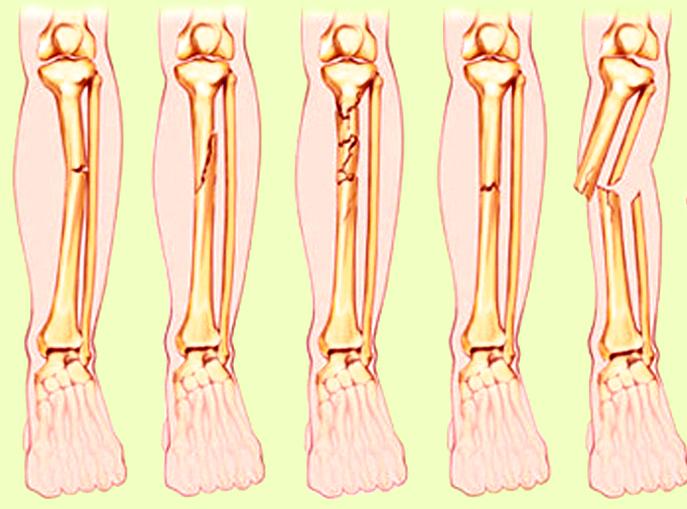

Jenis Dan Kategori Tulang Patah

Jenis Dan Kategori Tulang Patah

Topik 4 sains sukan

Topik 4 sains sukan

Fraktur - Jenis û Penyebab dan Pengobatan - IDN Medis

Fraktur - Jenis û Penyebab dan Pengobatan - IDN Medis